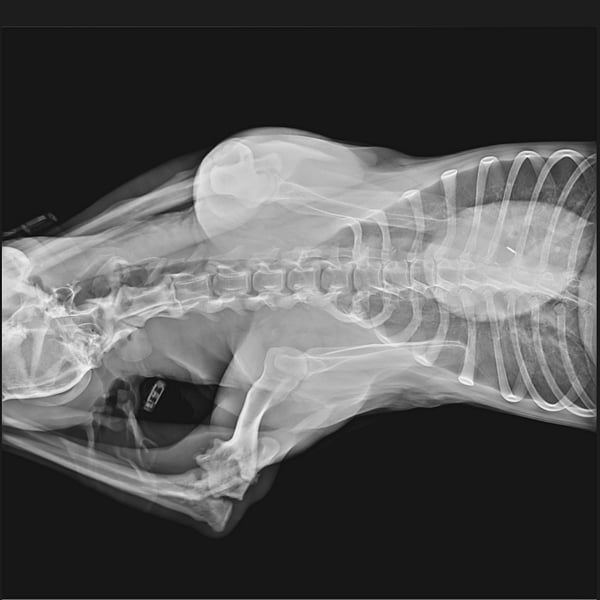

Einem unserer rumänischen Tierschützer fiel in der Tötung ein Hund auf, der am Bein verletzt zu sein schien. Dieser Hund lag sonst immer in einer Ecke, an diesem Tag sah er ihn zum ersten Mal in Bewegung - humpelnd. Wir wurden gebeten, ihn schnellstens herauszuholen, damit er einem Arzt vorgestellt werden konnte. ... der Arme tat uns so leid, aber erst einmal wollte man ihn nicht herausgeben, da angeblich seine Wartefrist noch nicht abgelaufen war. Als Druck gemacht wurde, durfte Miro - wie er nun genannt wird - diesen schrecklichen Ort dann doch verlassen. Wir haben Miro sofort röntgen lassen als er aus der Tötung geholt wurde. Der Tierarzt informierte uns, dass Miro eine Fraktur im Ellenbogen hat. Er muss schreckliche Schmerzen gehabt haben, das schlimme aber ist, dass diese Fraktur mittlerweile schon zu alt ist, sodass eine Operation nicht mehr in Frage kommt. Wie lange muss dieser arme Kerl mit schrecklichen Schmerzen ausgeharrt haben? Warum hat ihm niemand geholfen? Einen Arzt informiert? Dann hätte sein Bein behandelt werden können...

Wir haben die Röntgenbilder verschiedenen Ärzten gezeigt, die Antwort war dieselbe. Eine Operation ist aufgrund des Alters der Verletzung nicht mehr möglich, eine Versteifung des Gelenks nicht erforderlich, da er das Bein benutzt. Eine Bandage wird Miro zur Unterstützung ausreichen.